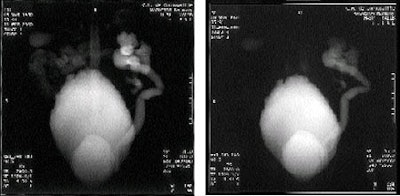

Se ha utilizado con éxito el zumo de arándanos como agente de contraste en el pasado. Investigadores de Japón descubrieron que "mejoraba la confirmación del tracto gastroduodenal, independientemente de la intensidad del campo magnético, y podía adaptarse para la resonancia magnética de secuencia espín-eco rápida (Nippon Igaku Hoshasen Gakkai Zasshi, June 1994, Vol. 54:6, pp.539-541).

Radiólogos suizos del Hospital Universitario de Zurich probaron la viabilidad de la gastrografía por resonancia magnética tras la administración oral de zumo de arándanos enriquecido con gadolinio. Descubrieron que la mezcla permitía la visualización exoscópica y endoscópica virtual del estómago (European Radiology, January 1999, Vol. 9:1, pp.73-77).

El zumo de arándanos mejoraba la visualización del conducto colédoco y del conducto pancreático en la colangiopancreatografía por resonancia magnética, de acuerdo con un estudio publicado en el Journal of Computer Assisted Tomography (March-April 2000, Vol. 24:2, pp. 229-234).

Rivoal manifestó que su grupo es el primero que utilizó el zumo de arándanos para la urografía por resonancia magnética pediátrica, y que el protocolo se utiliza de forma habitual en su centro. Rivoal agregó que ha utilizado con éxito la jalea de arándanos sobre pan de centeno como agente de contraste para la resonancia magnética en adultos y niños mayores, observando que el centeno también es rico en manganeso.